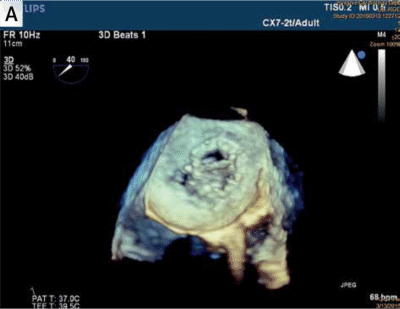

Zamknięcie przecieków zastawkowych metodą przezskórną stanowi duże wyzwanie kliniczne, szczególnie ze względu na złożoność anatomiczną kanałów PVL (ang. paravalvular leak – przecieków zastawkowych) oraz ryzyko kolizji okludera z mechanicznymi elementami zastawki. Zespół badawczy postawił sobie za cel ocenę możliwości wykorzystania danych z echokardiografii przezprzełykowej (3D-TEE) do stworzenia modeli 3D, które pozwoliłyby lepiej dobrać typ i rozmiar okludera przed zabiegiem.

Zespół z GCM i ŚUM wykorzystał dane z echokardiografii 3D-TEE, które po konwersji do plików 3D, dzięki segmentacji w oprogramowaniu powiązanym z drukarką 3D (slicer), zostały wydrukowane w rzeczywistej skali na drukarce Stratasys Objet 30 (v.3) w technologii PolyJet.

Modele drukowane w technologii 3D na podstawie danych z TEE umożliwiają dokładne odwzorowanie przecieku i symulację interakcji okludera z tkankami oraz zastawką. Zdecydowanie wpływa to na skuteczność i bezpieczeństwo zabiegów.

Modele wydrukowane na drukarce Objet 30 odwzorowały strukturę przecieków z wystarczającą precyzją – dzięki temu zespół medyczny mógł realistycznie przetestować różne konfiguracje okluderów jeszcze przed zabiegiem. To znacząco wpłynęło na trafność doboru strategii leczenia.

Górnośląskie Centrum Medyczne i Śląski Uniwersytet Medyczny wdrożyły druk 3D PolyJet od Stratasys do planowania zabiegów zamknięcia przecieków okołozastawkowych. Technologia pozwoliła na stworzenie anatomicznie wiernych modeli serca na podstawie danych z echokardiografii 3D-TEE.

Modele drukowane w skali 1:1 umożliwiły symulację zabiegów, testowanie różnych typów i rozmiarów okluderów oraz ocenę ich interakcji z zastawką i tkankami. W 7 z 8 przypadków dobór okludera na modelu pokrywał się z decyzją kliniczną, co przełożyło się na większe bezpieczeństwo i skuteczność procedur.